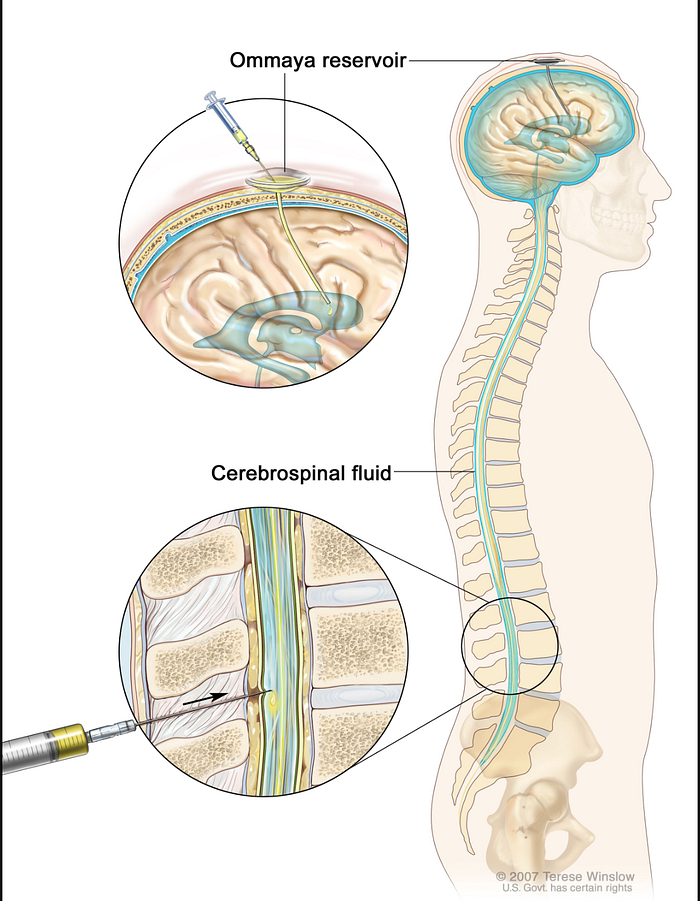

2) Intrathecal chemotherapy

This treatment involves injecting chemotherapy drugs into the fluid-filled space between the thin layers of tissue that cover the spinal cord and brain.

There are two different ways to do this. One way is to inject the drugs into an Ommaya reservoir (a dome-shaped container that is placed under the scalp during surgery; it holds the drugs as they flow through a small tube into the brain). The other way is to inject the drugs directly into the cerebrospinal fluid (CSF) in the lower part of the spine.

The main issue with the Ommaya reservoir is that surgery is required to both implant and remove the reservoir itself, raising the likelihood of getting an infection or other side effects. Furthermore, you are limited in your activities as you can’t do anything that would risk damaging the reservoir (e.g. contact sports) and you must be constantly wary about hitting your head. Here is a breakdown of all of the risks involved with this procedure:

- There is a small risk that you could bleed into your brain.

- There is a small risk that you could have some loss of function.

- There is a small risk that you could get an infection in your brain.

- The Ommaya reservoir may need to be adjusted. To make sure it’s in the right place, you will get a computed tomography (CT) scan the day after your surgery. If your reservoir isn’t in the right place, you may need to undergo another surgery to correct it.

- The Ommaya reservoir may fail. To make sure your Ommaya reservoir is working, a CSF flow study may be done after your surgery.